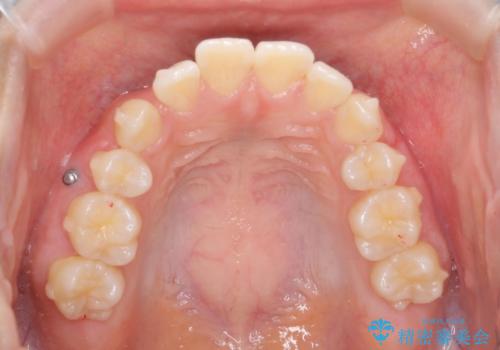

- 5年前にワイヤー矯正治療を終了したが、突き出たように見える前歯の仕上がりが気に入らず、再矯正治療を希望され来院されました。

マイクロインプラントを用いた遠心移動とIPRを行うことによる前歯の突出感の改善をマウスピース矯正治療で計画します。

突出していた前歯の角度が大きく改善し、審美的な仕上がりに満足いただくことができました。